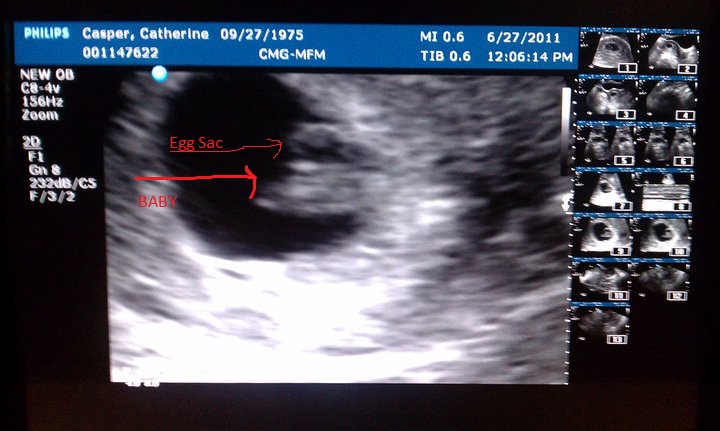

Wes and I are expecting our second baby. All my blood work up came back today as excellent. And I had an ultrasound this past Monday. Baby is progressing, perfectly. I was able to see the heart beating on the monitor and it was amazing! 152 beats a minute. Very strong and healthy! I just wish the stomach sickies would end and my vertigo would go away. Other then that, it's been okay. LOL

Due on Feb. 14th, 2012. Yes, Valentine's Day!

Attached Images

File Type: jpg Baby Casper 6-27-2011.jpg (93.2 KB, 396 views)